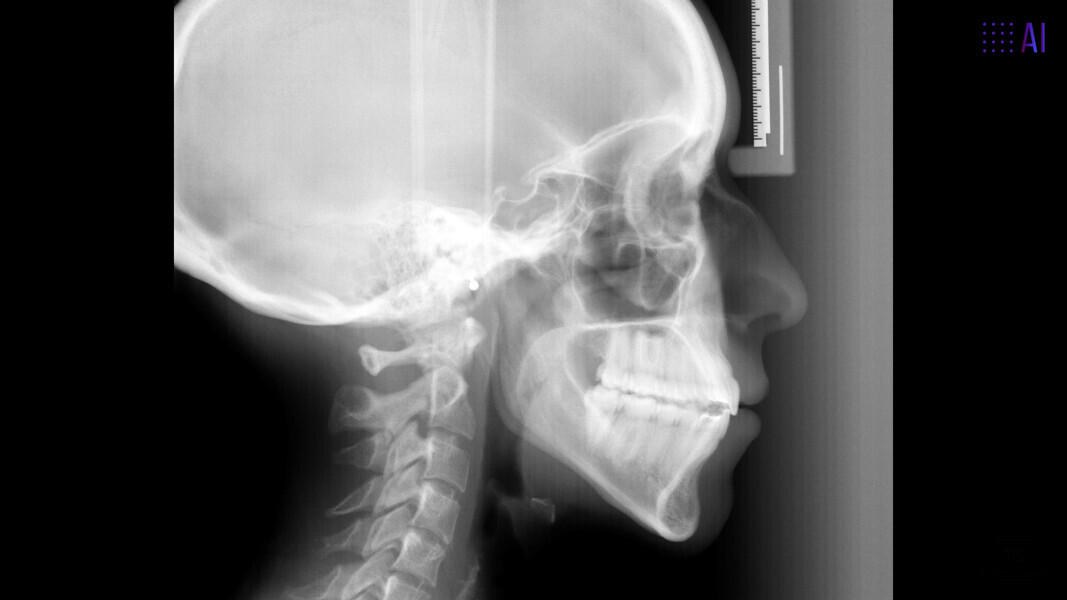

The 23-year-old dolichofacial female patient complained of not being able to chew properly. Facial examination showed a convex profile, an enlarged lower facial height, and a skeletal Class III malocclusion (Figs. 1–3). Intra-oral examination revealed an Angle Class III right subdivision malocclusion, anterior open bite, no overjet and a maxillary dental midline deviated about 3 mm to the right compared with the mandibular dental midline (Fig. 4). The panoramic radiograph confirmed previous extraction of the maxillary right first premolar and the presence of all four third molars (Figs. 5 & 6).

Although Class III elastics tend to extrude the maxillary molars and generate clockwise mandibular rotation, aligners allow us to prevent these complications, since we have better control over tooth movement, enabling us to counteract unwanted dental movements. In this case, an intrusion of the posterior teeth was planned, which would generate anticlockwise rotation of the mandible in an anticlockwise direction. This vertical control led to the closure of the anterior open bite and the reduction of the lower facial height, thereby improving the facial profile.